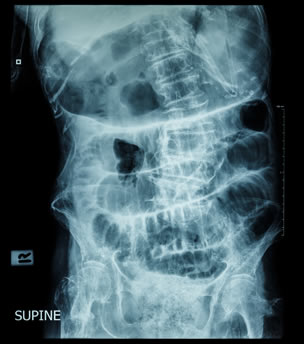

Οι απλές ακτινογραφίες κοιλίας αποτελούν την πιο σημαντική διαγνωστική δοκιμασία στον ειλεό. Πρέπει να γίνονται σε όρθια και σε ύπτια θέση. Αναδεικνύονται διατεταμένες έλικες λεπτού εντέρου (ημισεληνοειδείς διαυγάσεις) σε διάταξη κλίμακας στην ύπτια ακτινογραφία και υδραερικά επίπεδα, τα οποία είναι εμφανή στην απεικόνιση σε όρθια θέση.

Ακτινογραφία σε ύπτια θέση

Αυτά τα ευρήματα μπορεί να είναι ελάχιστα ή και απόντα στην πρώϊμη φάση της απόφραξης, στην εγγύς απόφραξη, την απόφραξη «κλειστής έλικας», ιδιαίτερα σε ισχαιμική περίσφιξη της τελευταίας, και σε περιπτώσεις που οι έλικες είναι γεμάτες με πολύ εντερικό υγρό και περιέχουν λίγο αέρα. Σε απόφραξη πέραν του 24ωρου, ο αέρας και τα κόπρανα έχουν κενωθεί από το παχύ έντερο, και αυτό φαίνεται στην απλή ακτινογραφία. Στην πρώϊμη φάση ωστόσο, αλλά και στις περιπτώσεις που η απόφραξη είναι μερική και ο ειλεός ατελής, κάποια ποσότητα αέρα ανευρίσκεται στο παχύ έντερο, και αυτό αποτελεί ένα από τα στοιχεία που διαχωρίζουν τον πλήρη από τον ατελή ειλεό.